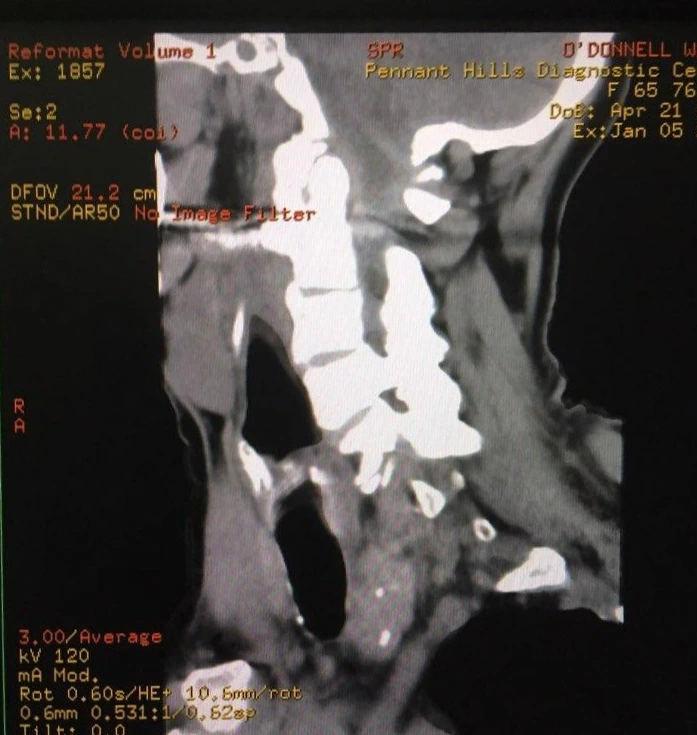

제이 : 방사선사는 일반적으로는 X-Ray 촬영을 하는 사람으로 알려져 있는데 ‘영상의학’을 전반적으로 아우르는 테크니션이라고 할 수 있어. X-Ray를 시작해서 경력이 쌓이면서 수술실에서 C-Arm 엑스레이, CT 스캔 MRI, 초음파 등의 검사를 진행하고 병변이 보이는 응급한 경우 의사에게 바로 리포트를 해서 조치를 취하게 해. 호주에서 2009년 영상의학 학사학위 유학을 시작하며 이 일에 연을 맺었어. 실무 경력은 한국에서 방사선 촬영병으로 2년, 호주의 요양병원에서 CARE NERSE로 4년, 그리고 졸업 후 방사선사로 1년 차로 총 7년 째 의료계에 종사하고 있어.